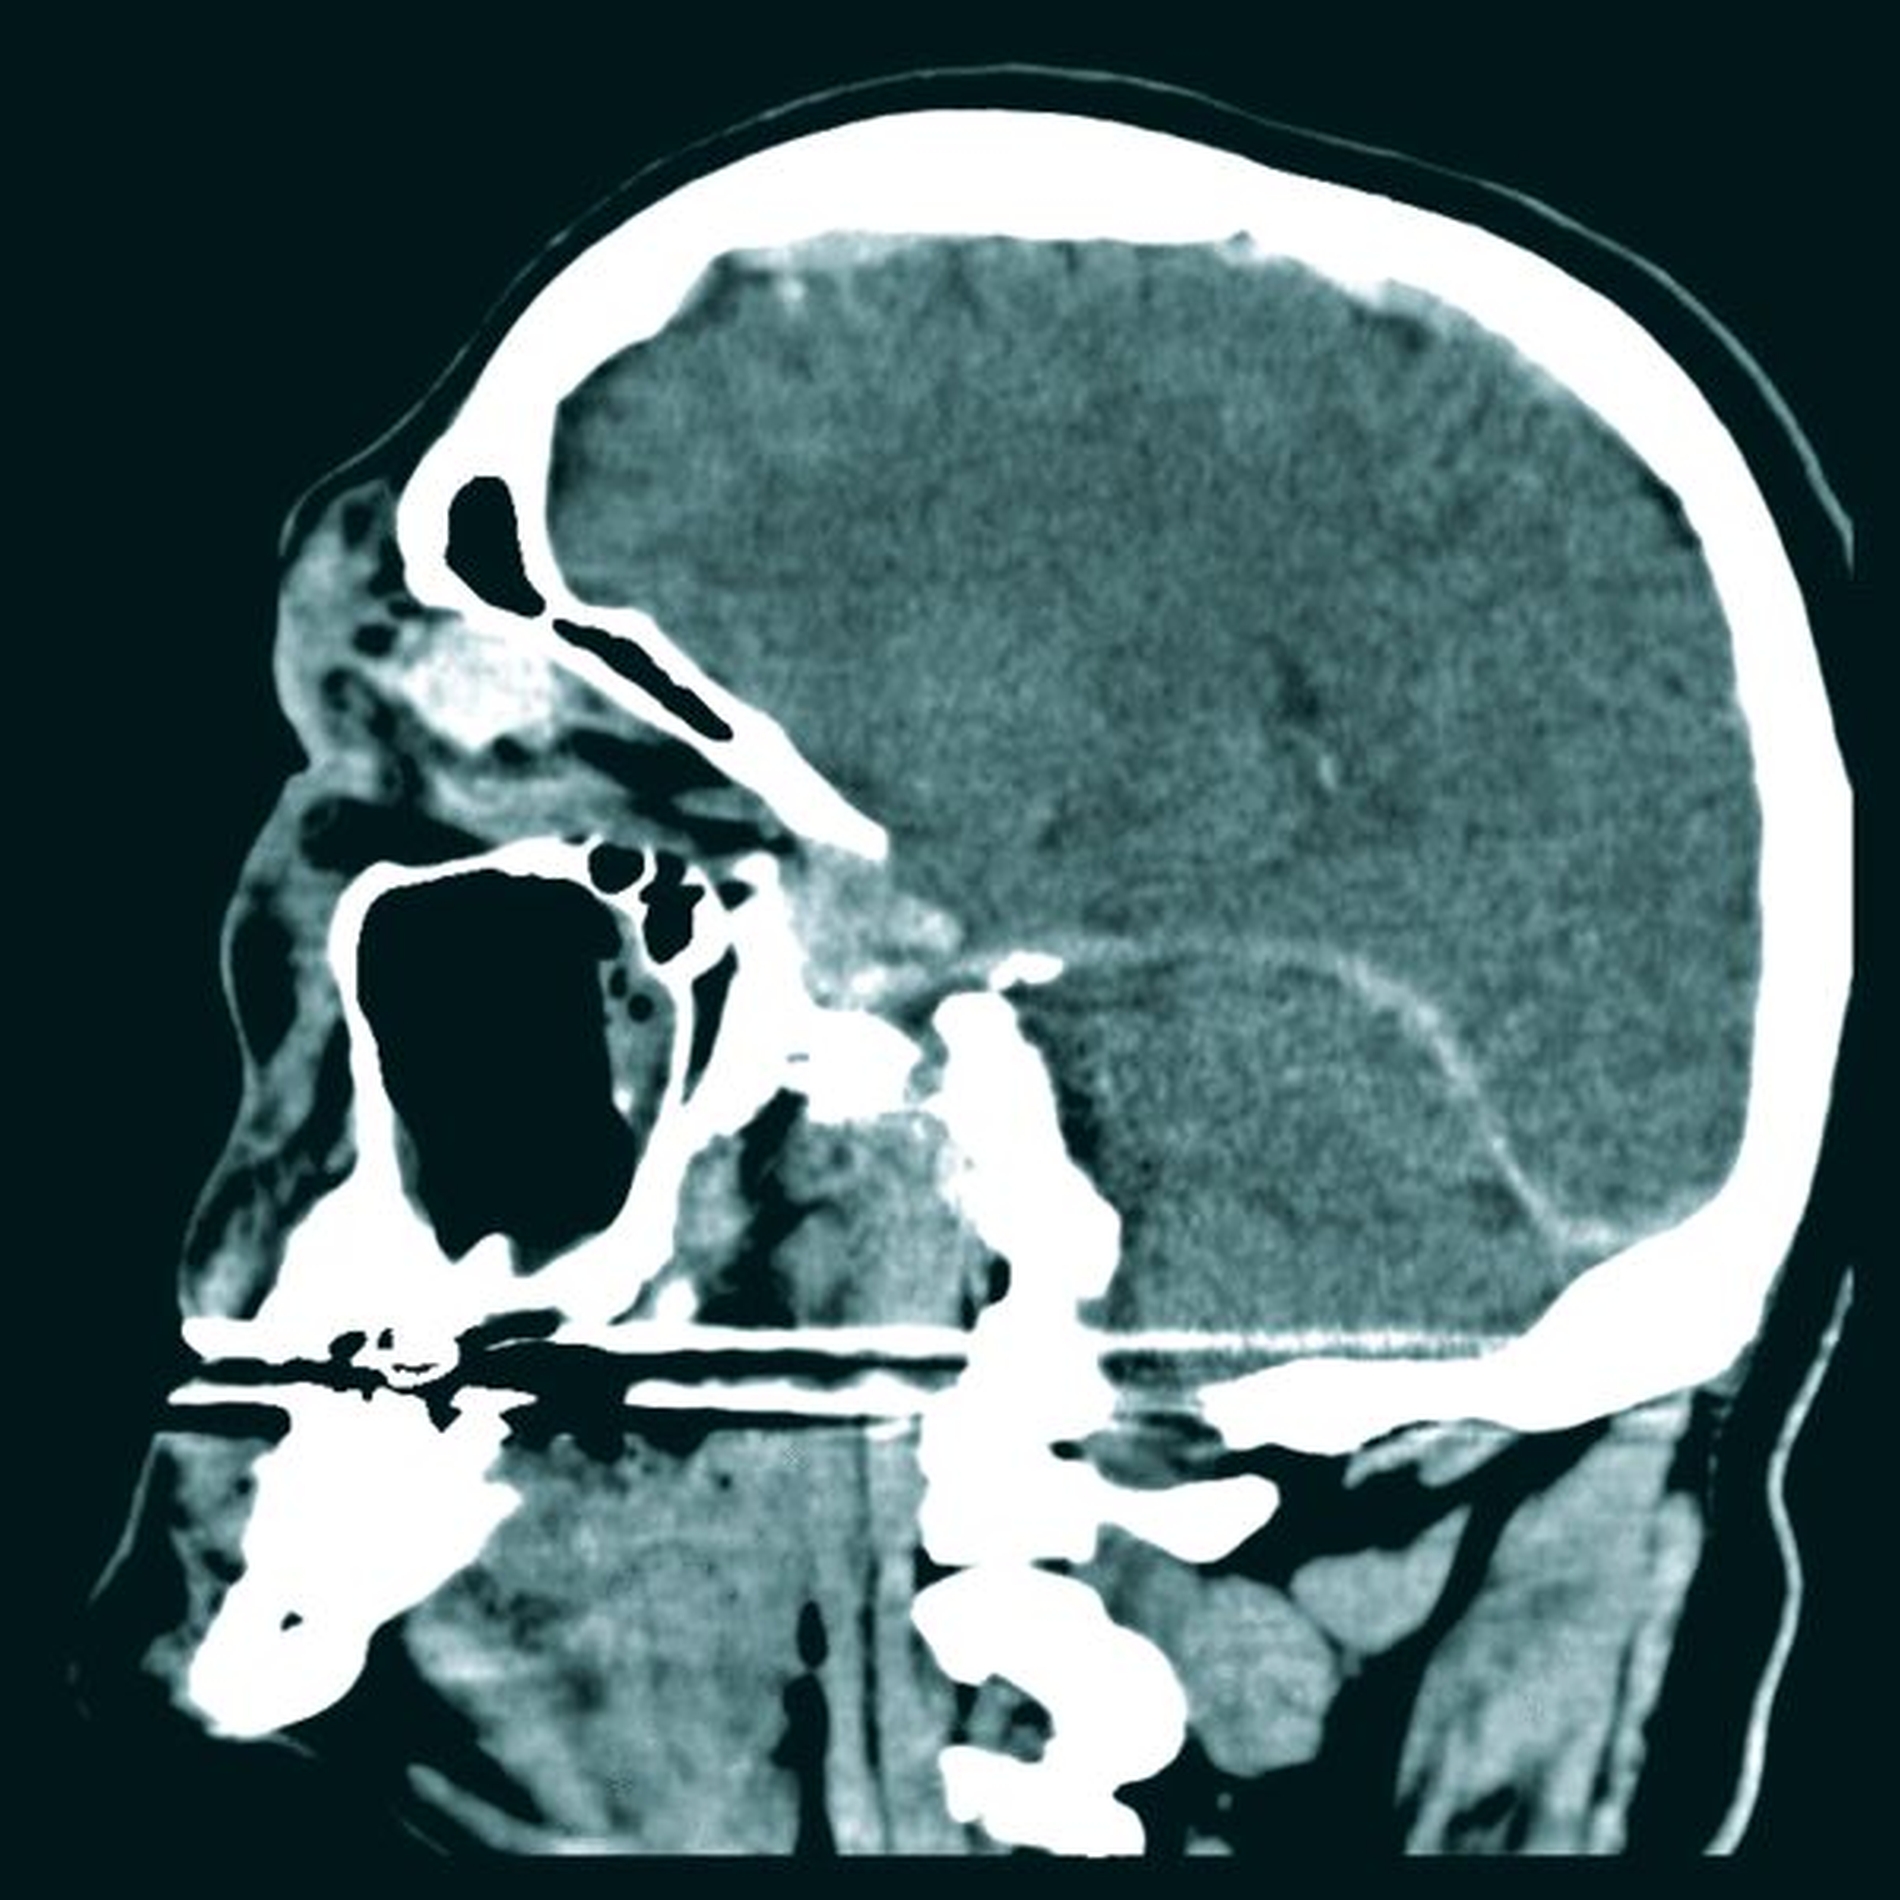

Klinisch zeigten sich am rechten Auge ein deutlich verminderter Visus bei eingeschränkter Motorik in allen Achsen mit ausgeprägtem periorbitalem Hämatom sowie ein Hyposphagma (subkonjunktivale Einblutung). Weiterhin lag eine Anisokorie vor, die rechte Pupille war weit und reagierte nicht mehr auf Lichtreize (Abbildung 1). Daher erfolgte umgehend eine CT-Untersuchung der Orbita, die eine Fraktur der rechten medialen Orbitawand am Übergang zum Orbitadach und am Bereich des Orbitatrichters an der Lamina papyracea mit Fragmentimpression in die Ethmoidalzellen nachwies. Weiterhin lag ein Hämatom von 3,3 cm x 1,4 cm an der medialen Orbitawand cranial des M. rectus medialis bis nach retrobulbär reichend vor. Dies hatte bereits zu einer Protrusio bulbi geführt. Der linke Orbitaboden war ebenfalls frakturiert (Abbildungen 2a und 2b).